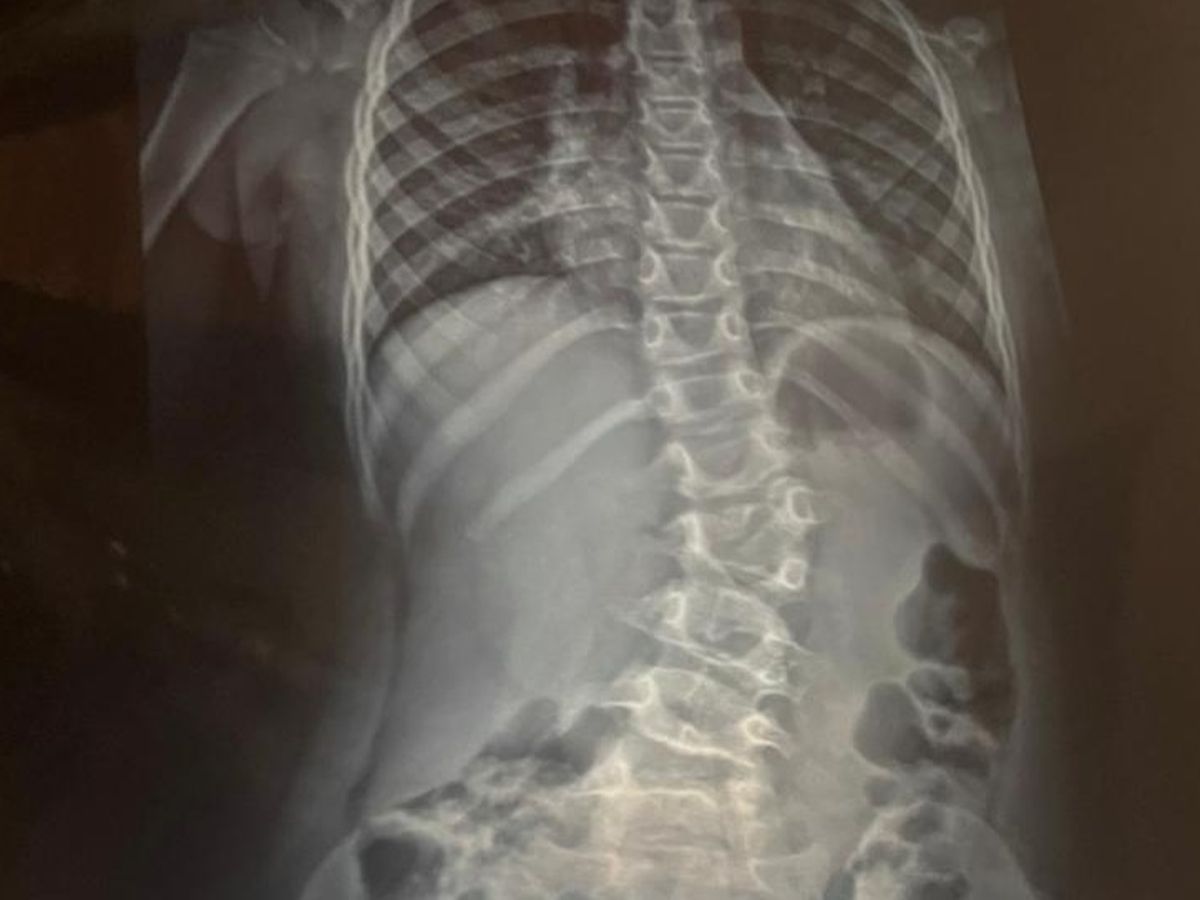

At just three months in the womb, during a routine ultrasound, Emily was diagnosed with thoracic lumbar scoliosis. We were told it wouldn't correct itself, that instead it would worsen, and that surgery would be necessary when she turned ten.

However, our little girl has grown so much in the past few years, and her scoliosis has progressed faster. At only 7, she's already experiencing major pain. Surgery is no longer something we can postpone. It's needed now.